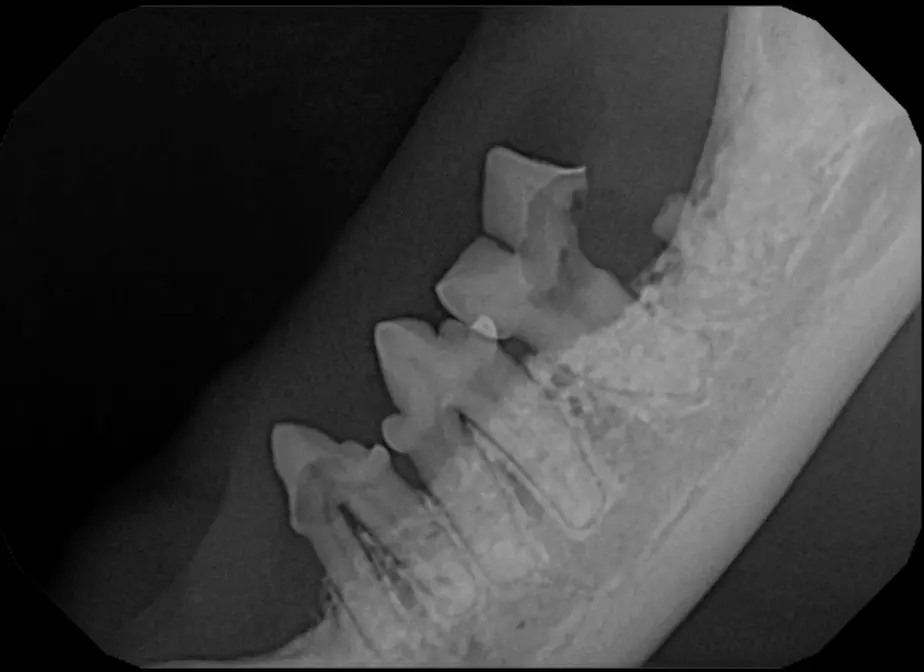

The Center now provides advanced imaging via cone beam CT. Cone beam CT is excellent for visualization of bony structures of the skull, nasal cavity, teeth, and ears. Cone beam CT is especially helpful for diagnosing dental disease and evaluation of jaw fractures. It can also be useful for evaluating the sinuses and tympanic bulla. Cone beam CT can be used in conjunction with nasal biopsy and culture to evaluate nasal discharge whether chronic or acute.

Pets can be involved in trauma that can cause fractures to their head, teeth, and jaw bones. Correctly repairing these fractures is extremely important for your pet to have normal function of their mouth. If a jaw fracture is allowed to heal in an abnormal position, your pet may have great difficulty chewing and can be in significant pain. Many fractures can be successfully treated with minimally invasive oral procedures, but more complicated cases may require bone plating techniques. The Center offers cone beam CT imaging which provides extremely detailed images of the bones of the head and skull. Advanced imaging with CBCT facilitates selection of the best surgical technique to get your pet back to eating and comfort as soon as possible.